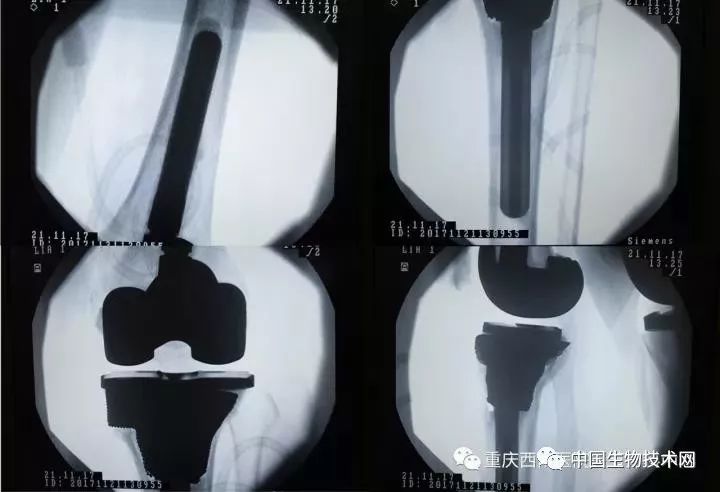

术前X光片